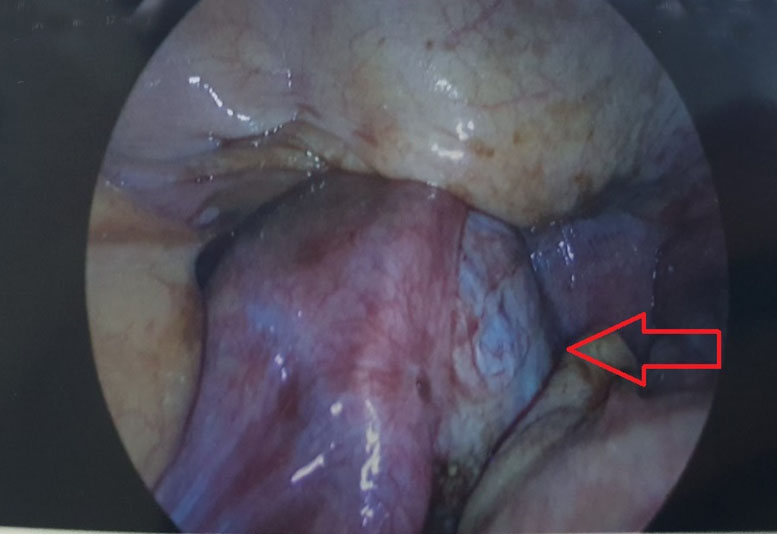

She had a laparoscopy appendectomy the next day. The appendix and mesoappendix appeared thickened with extensive endometriosis in pelvis and left ovary endometrioma were visualized (Figure 4 and Figure 5). The appendix was removed and she was discharged home the next day. Her histology result showed two foci of endometrial present in the subserosa of the appendix with surrounding endometrial stroma and no atypical features seen. There was also mucosal lymphoid hyperplasia but no transmural neutrophilic infiltrate which indicated no acute inflammation of the appendix.

Figure 4: Intraoperative photo: hemoperitoneum from retrograde menstruation.